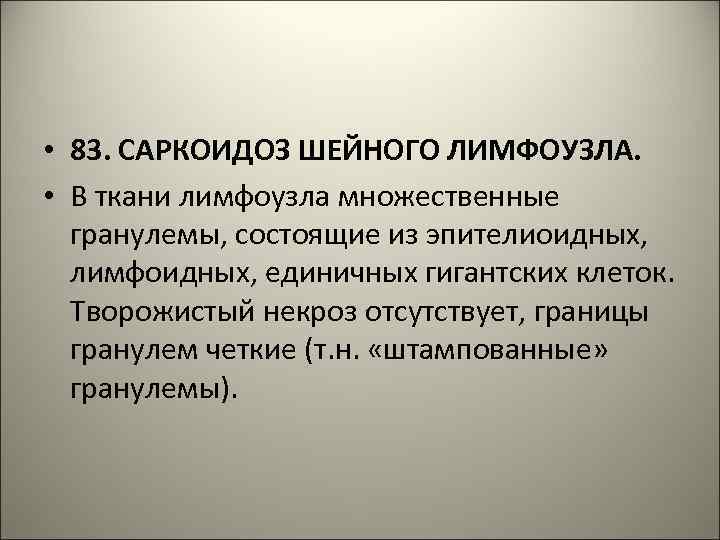

• 83. САРКОИДОЗ ШЕЙНОГО ЛИМФОУЗЛА. • В ткани лимфоузла множественные гранулемы, состоящие из эпителиоидных, лимфоидных, единичных гигантских клеток. Творожистый некроз отсутствует, границы гранулем четкие (т. н. «штампованные» гранулемы).

83. САРКОИДОЗ ШЕЙНОГО ЛИМФОУЗЛА (Х 100).

83. САРКОИДОЗ ШЕЙНОГО ЛИМФОУЗЛА (Х 400).